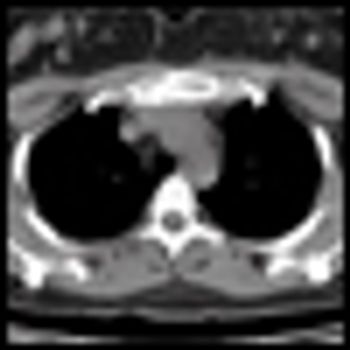

An asymptomatic 45-year-old woman presented for a screening mammogram and was noted to have a soft-tissue opacity with calcifications in the left breast. Ultrasound revealed a highly suspicious mass.